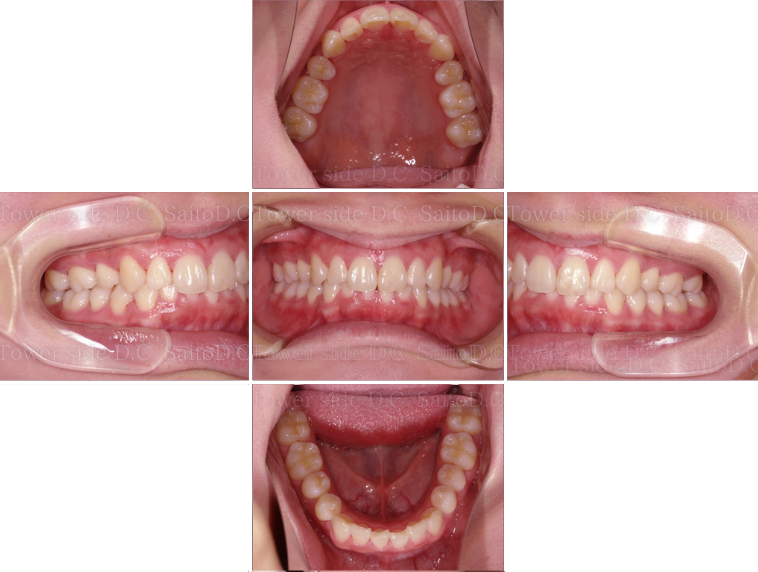

症例8CASE 8

|20代歳(女性)|

インビザラインエクスプレス

症例(施術前)

症例(施術後)

主訴 上顎側切歯の出っ張りを治したい

状況

• 上顎前歯叢生

• 上顎切歯口蓋側傾斜

• 下顎叢生

治療費 519,200円(税込)(自由診療)

治療期間 8ヶ月

治療内容 歯のディスキングを行い歯列を整えた。叢生は改善され、その後保定装置(リテーナー)を使用し安定している。

リスク

• 歯根呼吸や、歯根の成長が阻害される可能性、歯髄が壊死する可能性。

• 歯の痛み、顎の痛み、虫歯、歯周病、矯正器具により口腔粘膜の傷、喋りにくさが生じる可能性。

• 矯正治療後は、リテーナーを使用しないと歯の位置に後戻りが生じる可能性。